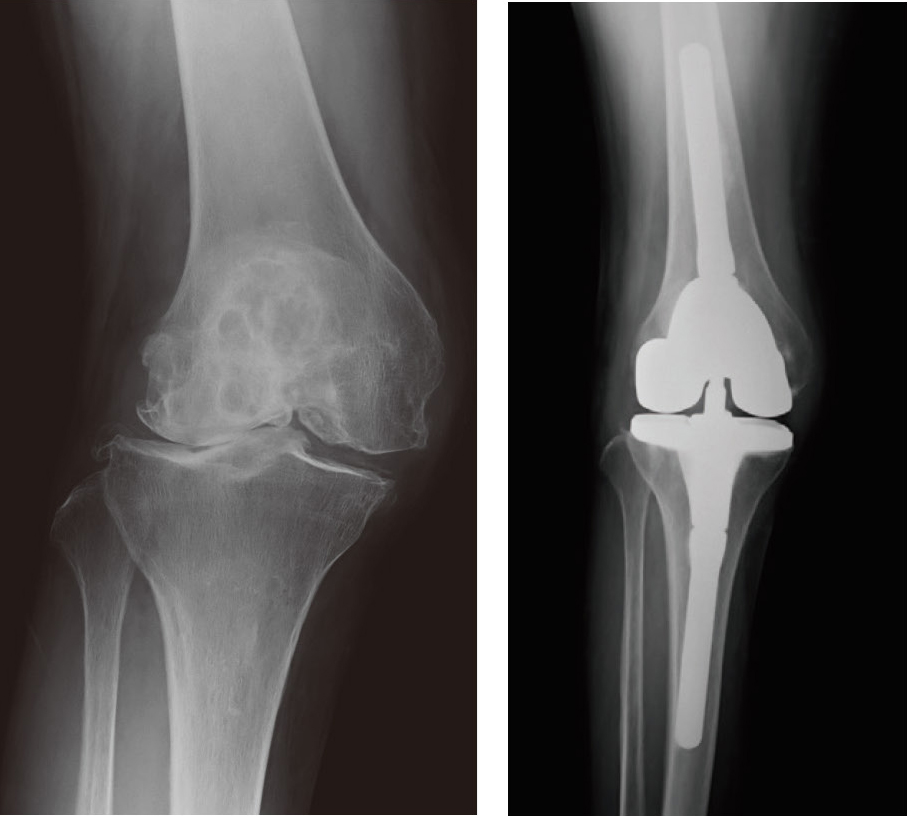

術前 術後

拘束性の強い人工膝関節置換術の

レントゲン

後十字靭帯が拘縮している場合の

人工膝関節置換術のレントゲン

部分置換術のレントゲン

変形して傷んだ膝関節の骨の表面を取り除き、金属とポリエチレンでできた人工関節と置き換えることで、膝を安定させ、円滑な動きを取り戻す手術です。膝全体が大きく変形して日常生活に大きな支障をきたすほどの強い痛みがある変形性膝関節症末期の人に行う、膝関節治療の最終手段ともいえる手術です。除痛効果に優れ、入院期間が短くて済むのが特長です。

大きく分けて4種類あります。①傷んでいるのが片側だけで変形も比較的軽度な人にはより負担の少ない片側だけ置き換える部分置換術を。②内側も外側も傷んでいるが前十字靭帯と後十字靭帯がともに機能している人には、それを温存できる人工関節を使った全置換術を。①と②は靭帯が温存できるので、安定した自然な膝の動きが獲得できます。③骨の変形が強く後十字靭帯が拘縮している場合は、後十字靭帯がなくても機能する人工関節を。④十字靭帯だけでなく、横方向の安定性を得るのに重要な内側側副靭帯が機能していない場合や骨の欠損が強い場合は、拘束性の強い人工関節を。③や④のケースでは術前の膝の状態がかなり悪いことも多いのですが、術後は買い物や旅行くらいであれば不便を感じないレベルに改善します。